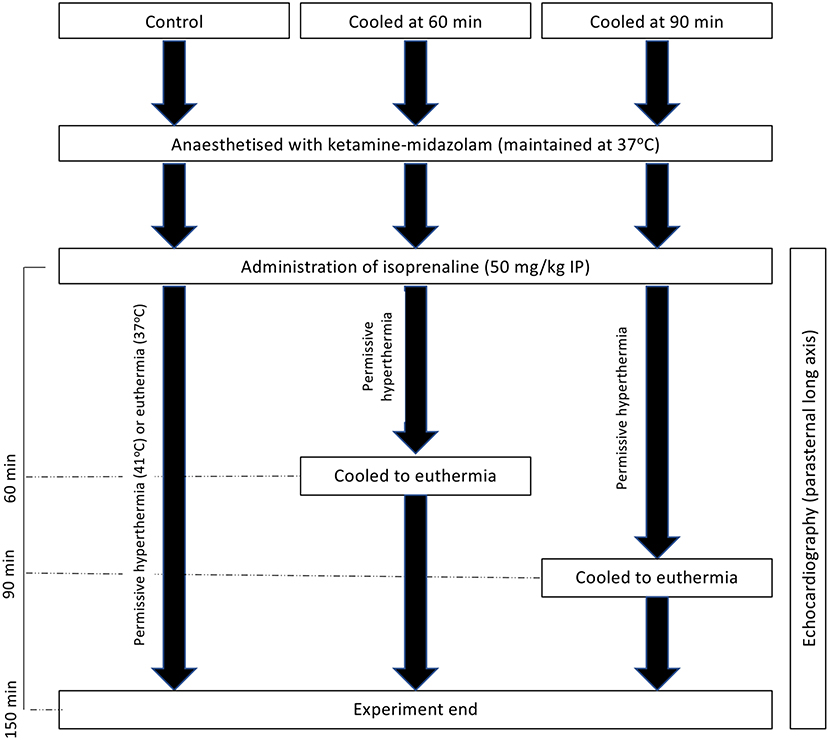

Before catecholamine administration, body temperature was maintained between 37 and 38°C using a homeothermic temperature monitor, rectal temperature probe, and heating blanket (Harvard Apparatus). Heating was maintained at a similar level after the administration of isoprenaline, with a new set-point of 41°C used. Cooling, if required at either 60 or 90 min post-isoproterenol administration (Figure 1), was achieved through the removal of external heat sources and the application of ice packs to the abdomen until the rectal temperature was back in the euthermic zone, after which external heating was reapplied as required to maintain euthermia. For experiments shown in the Supplementary Figures, male rats were randomized to either of two groups and subsequently received 50 mg/kg isoprenaline intraperitoneally. Body temperature was maintained at 37.5 ± 0.5°C (normothermia) for the duration of the experiments in the first group whereas in the second group body temperature was first allowed to rise spontaneously and, starting at 15 min post isoprenaline, was maintained at 41 ± 0.5°C (hyperthermia) for the remainder of the experiment. Extent of akinesia was traced in the long axis and expressed as percentage of total LV endocardial length.

Figure 1. Experimental schematic of hyperthermic experiments with and without cooling to 150 min post-isoprenaline administration.